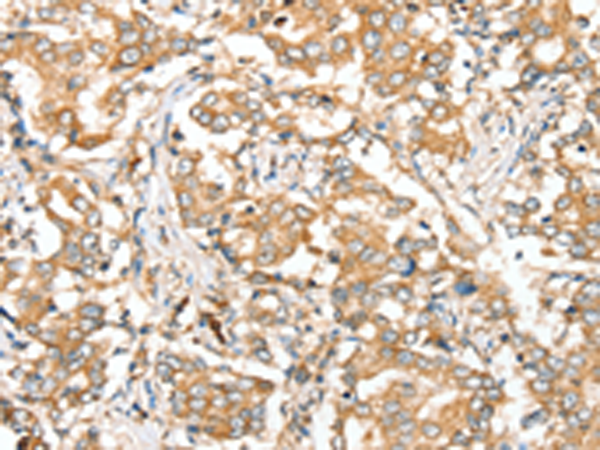

分类: 科研抗体货号: P12174别名: SIR2L4应用: IHC反应种属: Human, Mouse